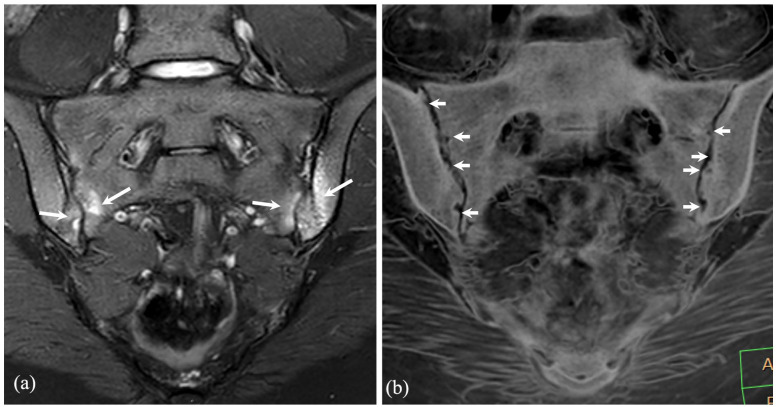

由于技术创新以及对安全和以患者为中心的护理的日益重视,儿童肌肉骨骼成像领域正在取得重大进展。这篇综述探讨了成像方式的最新发展,如先进的磁共振成像、超声创新和人工智能应用。重点包括放射摄影和计算机断层扫描中的辐射剂量降低技术,增强的诊断工具,如对比度增强超声和超高频成像,以及用于病理检测和工作流程优化的人工智能集成。采用先进的方法,如全身磁共振成像和类似计算机断层成像的磁共振成像序列,提高了诊断的准确性,最大限度地减少了辐射暴露,并扩大了非侵入性成像的能力。新兴技术,包括光子计数检测器计算机断层扫描和基于深度学习的重建,正在通过平衡精度和安全性来改变临床实践。人工智能应用正在重塑诊断方法,自动化复杂的评估,并提高效率,尽管外部验证和有限范围等挑战仍然存在。功能成像的进步,如弥散加权成像和正电子发射断层扫描-磁共振成像的整合,正在增强疾病的表征和治疗计划。本综述强调了这些创新的临床影响,强调了标准化方案、跨学科合作和持续研究的必要性,以解决辐射安全和人工智能集成方面未满足的需求。它旨在为医疗保健专业人员提供知识,以利用这些进步改善儿童肌肉骨骼护理的结果。

The field of pediatric musculoskeletal imaging is undergoing significant advancements due to technological innovations and a growing emphasis on safety and patient-centered care. This review explores recent developments in imaging modalities such as advanced magnetic resonance imaging, ultrasound innovations, and artificial intelligence applications. Highlights include radiation dose-reduction techniques in radiography and computed tomography, enhanced diagnostic tools like contrast-enhanced ultrasound and ultra-high-frequency imaging, and the integration of artificial intelligence for pathology detection and workflow optimization. The adoption of advanced methods like whole-body magnetic resonance imaging and computed tomography-like magnetic resonance imaging sequences has improved diagnostic accuracy, minimized radiation exposure, and expanded the capabilities of noninvasive imaging. Emerging technologies, including photon-counting detector computed tomography and deep learning-based reconstructions, are transforming clinical practices by balancing precision and safety. Artificial intelligence applications are reshaping diagnostic approaches, automating complex assessments, and improving efficiency, although challenges such as external validation and limited scope persist. Functional imaging advancements, such as diffusion-weighted imaging and positron emission tomography-magnetic resonance imaging integration, are enhancing disease characterization and treatment planning. This review underscores the clinical impact of these innovations, emphasizing the need for standardized protocols, interdisciplinary collaboration, and continued research to address unmet needs in radiation safety and artificial intelligence integration. It aims to equip healthcare professionals with the knowledge to leverage these advancements for improved outcomes in pediatric musculoskeletal care.